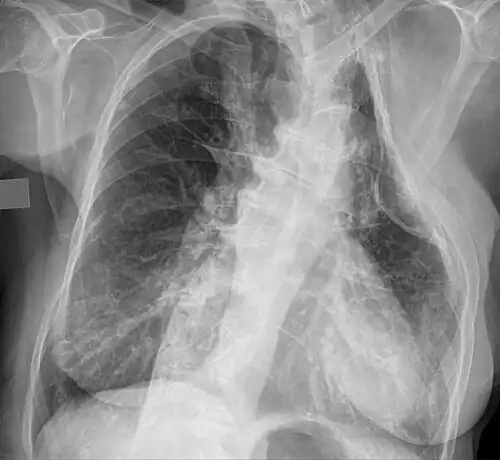

Eine Thorakoplastik ist ein operativer Eingriff, bei welchem Rippen oder Rippenteile einer Seite des Brustkorbs operativ entfernt werden, um die Lunge oder Teile der Lunge zum Kollabieren zu bringen.

Dieses Verfahren geht auf E. de Cérenville (1886)[1] zurück und wurde hauptsächlich zur Behandlung der Lungentuberkulose genutzt (und insbesondere von Ludolph Brauer, Paul Leopold Friedrich, Max Wilms und Ferdinand Sauerbruch weiterentwickelt),[2][3] verlor dann aber ab den 1950ern mit der Einführung wirksamer Antibiotika zunehmend an Bedeutung.

Die operative Mortalität betrug in der Vergangenheit bis zu 10 %. Die Folgen des Eingriffes konnten von einer Skoliose über verminderte Beweglichkeit bis zu Atemstörungen reichen.

Die Thorakoplastik wird heute z. B. noch zur Behandlung von bronchopleuralen Fisteln oder bestimmten Fällen der Skoliose verwendet.[4]